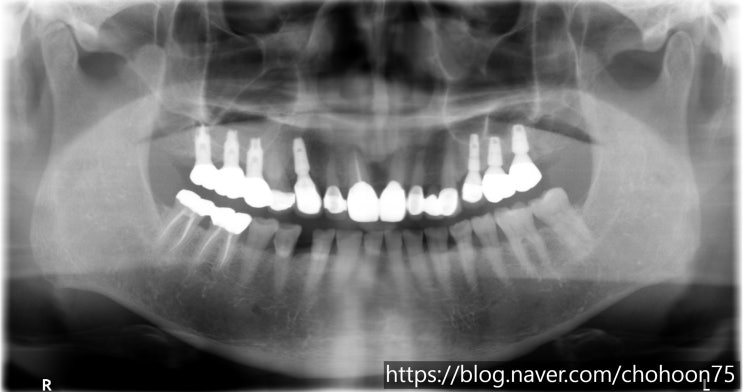

안녕하세요. 조훈 치과입니다. '상악동'은 위턱뼈 안에 존재하는 해부학적 구조물입니다. 이 조...